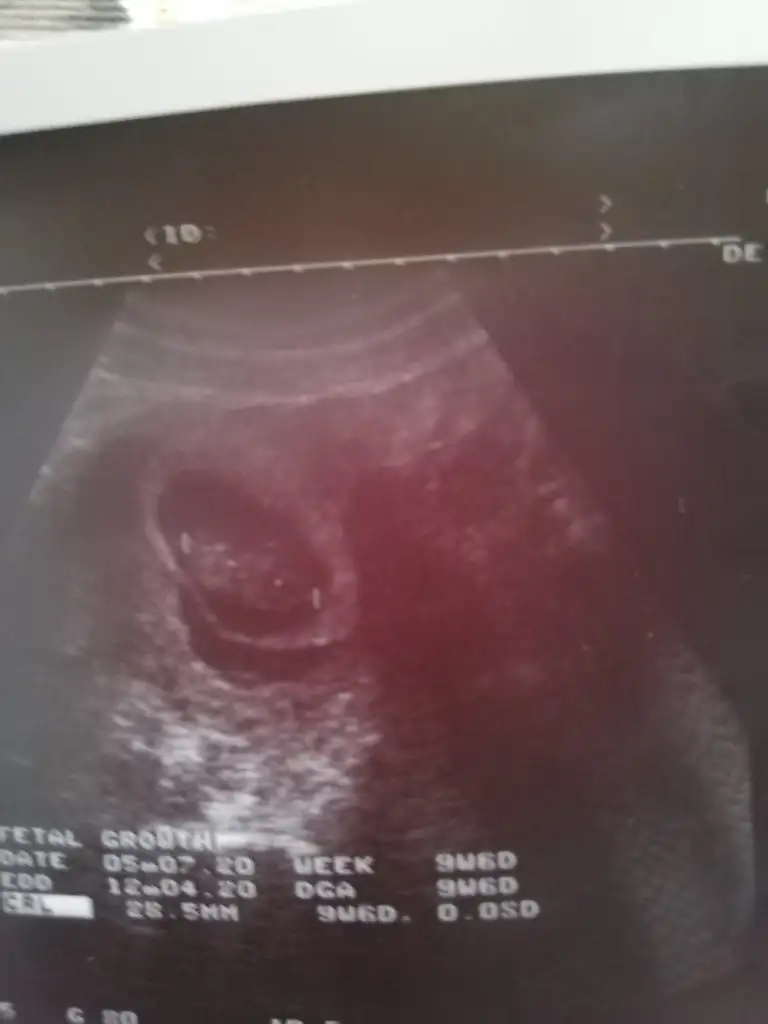

Bende öyleyim benim kanama alanı kesenin altında gözüküyor attım fotosunu doktor aslında olmaması lazım kanamanın ama yinede bebek iyi gelişiyor dedi hatta 2 gün önden gidiyor